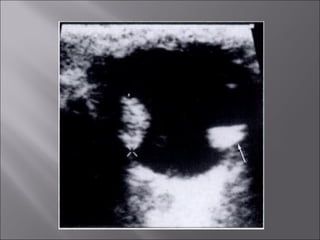

Ultrasound and CT scans provide anatomical images of the orbit, while color Doppler imaging provides visualizations of vascular structures and blood flow within lesions. These imaging techniques are used to evaluate a variety of orbital conditions involving blood vessels, infections, tumors, congenital issues, trauma, and more, and can help identify vascular disorders, thrombosis, treatment responses, and dynamic changes in benign tumors over time.